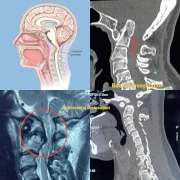

– Craniovertebral Junction Anomalies

We provide specialized cervical spine surgery in Thane for patients suffering from chronic neck pain, cervical disc prolapse, cervical spondylosis, and nerve compression syndromes. Surgical options may include cervical discectomy, fusion, or disc replacement depending on the condition. Our cervical spine experts ensure safe treatment with the goal of pain relief, mobility restoration, and nerve function preservation.